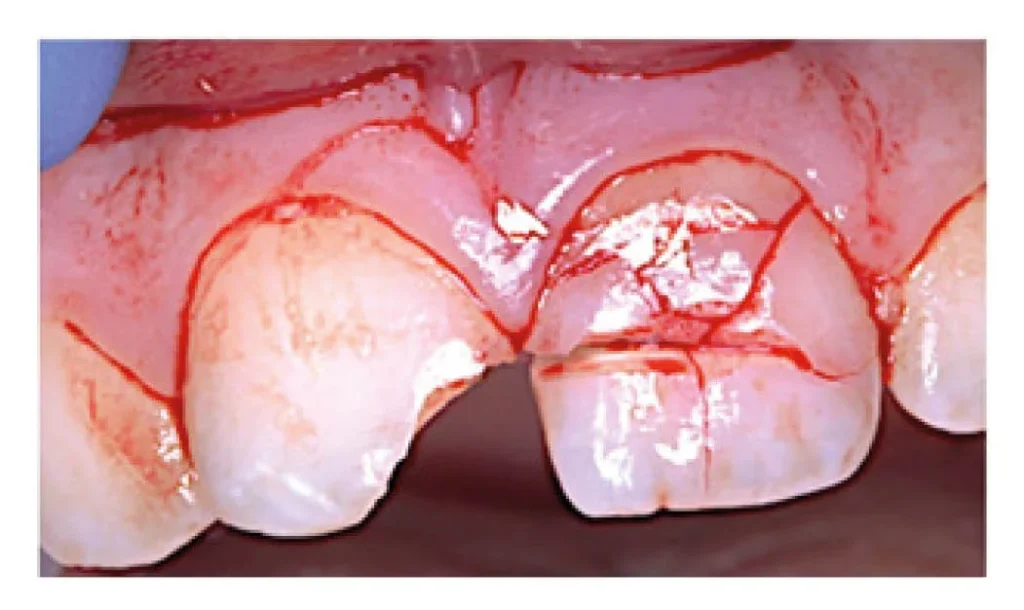

Treating dental trauma involves a fascinating array of techniques, each chosen to best address the specific damage incurred. For simple chips or minor fractures involving only enamel, the treatment is often straightforward: the sharp edge might be smoothed off, or a tooth-colored composite resin (bonding) can be used to rebuild the missing part, restoring both shape and function quickly and often invisibly. If the fracture extends into the dentin but not the pulp, bonding might still be an option, or a more extensive restoration might be needed depending on the size. If the fracture exposes the tooth’s nerve (pulp), then the treatment usually shifts dramatically towards preserving the tooth while dealing with the now-compromised nerve. This often necessitates root canal treatment, where the damaged or infected pulp is removed, the internal canals cleaned and disinfected, and then filled to prevent future infection. For teeth that are loose or displaced (luxated), the primary treatment is repositioning and splinting. The dentist will gently guide the tooth back into its correct position if it’s been moved. Then, a small, flexible splint (often made of composite resin and wire or nylon fishing line) is bonded to the injured tooth and usually the two teeth on either side, effectively acting like a tiny brace to hold the injured tooth stable while the supporting ligaments heal. The splint is typically kept in place for a few weeks, the exact duration depending on the type of luxation. An avulsed (knocked-out) tooth, if replanted quickly and correctly (as discussed in first aid), will also be splinted to allow the ligaments a chance to reattach. However, replanted teeth almost always require root canal treatment within a couple of weeks because the nerve and blood vessels supplying the pulp are severed during the avulsion event. In cases of severe fracture where the tooth cannot be restored, or if complications arise that threaten surrounding teeth or bone, extraction (removal) might be the only option. Soft tissue injuries like cuts to the gums or lips are cleaned and may require sutures (stitches) to help them heal properly. The specific treatment is a delicate balancing act, weighing the extent of the damage, the potential for healing, and the tooth’s long-term prognosis.

Trauma to the front teeth (incisors and canines) is particularly common, not just because they are at the front line and exposed to impact, but also because they are critical for both function (biting, tearing food) and aesthetics (your smile!). Treating trauma in this highly visible area carries the added weight of ensuring the outcome looks natural and blends seamlessly with the surrounding teeth. The specific treatment for front teeth trauma mirrors that of back teeth but with an increased emphasis on cosmetic results. Minor chips are frequently repaired using tooth-colored composite resin bonding. This material can be sculpted and polished to perfectly match the tooth’s original shape and color, often making the repair virtually invisible. For larger fractures, especially those involving dentin or the pulp, the treatment might range from extensive bonding to veneers or crowns, particularly if the remaining tooth structure is weakened or if significant discoloration occurs later. Crowns cover the entire tooth and can restore its form and function while masking discoloration, but they are a more invasive treatment option. Luxation injuries (loose or displaced teeth) in the front are treated with repositioning and splinting, just like back teeth, but splints on front teeth need to be placed carefully to allow for proper function and hygiene while maintaining stability. Avulsion (a knocked-out front tooth) is one of the most visually dramatic and urgent types of trauma, and prompt replantation (ideally within 30-60 minutes) is critical for survival. If successful, the tooth will be splinted, and root canal treatment will almost certainly be needed within a couple of weeks. Discoloration, particularly the tooth turning grey, is a common consequence of nerve damage in front teeth. If root canal treatment is needed for a discolored tooth, internal bleaching (bleaching applied inside the tooth) or external whitening followed by a veneer or crown may be used to restore the natural color. Because of the aesthetic stakes, treating front teeth trauma often requires not only clinical skill but also an artistic touch to ensure the repaired tooth looks as good as the original.

Finding yourself with a loose tooth after a knock to the mouth can be incredibly unsettling. It wiggles when you touch it, maybe hurts when you try to bite, and feels alarmingly unstable. The primary way dentists “fix” or stabilize a loose tooth caused by trauma (a luxation injury) is through a process called splinting. Think of a splint as a tiny, temporary brace for your tooth. The purpose of splinting is to hold the injured tooth firmly in its correct position within the socket while the damaged periodontal ligaments – the tiny fibers that anchor the tooth root to the surrounding bone – have a chance to heal and reattach. You should absolutely not try to tighten a loose tooth yourself at home with wires, glues, or any other improvised method; this can cause more harm than good and potentially introduce infection. Instead, see a dentist as soon as possible. The dentist will first assess the severity of the looseness and check for other damage like root fractures or nerve injury using X-rays and vitality tests. If splinting is appropriate, they will gently reposition the tooth if it’s been displaced. Then, they will apply a dental splint, which typically consists of a thin wire or fiber (like nylon fishing line) that is bonded using composite resin (tooth-colored filling material) across the injured tooth and usually one or two stable, uninjured teeth on either side. This creates a rigid or semi-rigid framework that keeps the loose tooth from moving while the ligaments recover. The duration of splinting varies depending on the type of luxation, but it’s typically kept in place for a few weeks (e.g., around 2 weeks for a subluxation, 2-4 weeks for a more severe luxation). During this time, it’s crucial to maintain excellent oral hygiene around the splint and eat a soft diet to avoid putting stress on the healing tooth. After the prescribed time, the dentist will gently remove the splint and check the tooth’s stability. Importantly, even after splinting, the injured tooth needs to be monitored long-term for signs of nerve damage or root resorption, as these can be delayed complications of luxation injuries.